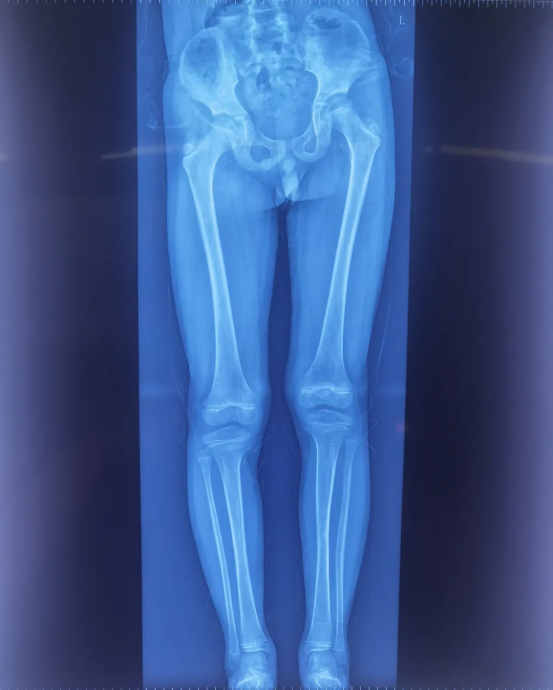

After screw placement, it is necessary to confirm whether their positions meet biomechanical requirements, as this directly affects the effectiveness of postoperative growth inhibition and the safety of skeletal development. Traditional 2D fluoroscopy cannot fully assess the screws’ positions in three-dimensional space, making it easy to overlook subtle deviations.

Perlove Medical’s 3D C-arm performs postoperative scans to verify screw placement from multiple dimensions: the relationship between the screws and the epiphyseal line

, any loosening or displacement and whether the femoral and tibial mechanical axes are approaching balance. If any subtle issues are detected, timely adjustments can be made to ensure optimal screw fixation. This postoperative 3D verification eliminates the observation blind spots in 2D imaging and serves as the final safeguard for surgical outcomes and long-term skeletal health.